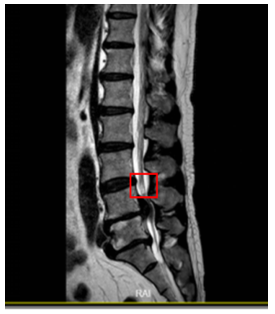

Typically, when spinal injuries involve the spinal cord, they can manifest as various degrees of signal changes. MRI can not only observe the morphological changes of acute SCI but can also precisely determine the degree of SCI based on changes in the spinal cord signal. Moreover, it can detect occult fractures and spinal cord edema, which significantly guides the formulation of treatment plans and the determination of prognosis. The MRI manifestations of SCI vary according to different lesion presentations. We consulted relevant literature on the MRI of SCI [20-22] and sought advice from professional spinal surgeons regarding its classification, finding two main types: one is based on the cause of injury, using cervical SCI as an example, which can be divided into Types I-IV, as shown in Figure 1 and Table 1; another classification method is based on the pathological changes in the spinal cord tissue, mainly divided into hemorrhage, edema, mixed type, etc., as shown in Table 2. From a medical professional perspective, the cause of injury in the first classification ultimately leads to pathological changes in the spinal cord that follow. For instance, cystic changes and glial scar formation, such types of pathological changes, usually occur during the recovery period, with early manifestations primarily being hemorrhage, edema, and mixed type. Therefore, this paper mainly uses the second classification method to detect the types of signal abnormalities in MRI and summarizes the characteristics of signal changes in SCI on MRI as shown in Table 2.

Figure 1. Imaging classification of acute cervical SCI (based on cause of injury)

Table 1. Imaging classification of acute cervical SCI (based on cause of injury)

Before conducting the experiment, the collected dataset needed to be preprocessed. First, two experienced spinal surgeons used LabelMe Toolbox-master software to annotate the lesion areas in the abnormal group for the training and validation sets to later verify the algorithm's effectiveness; the normal group was not marked. The annotation process used the LabelMe Toolbox-master tool for standard naming, framing the sample's name, size, location, etc., with bounding boxes and annotating image prompt information. The markings and annotations were saved in XML file format. As shown in Table 3, this indicates the annotated location of the lesion area for edematous SCI signal changes.

Table 3. Labeling of lesion areas for edematous SCI

1 |

L4/5 significant disc herniation with free compression of the spinal cord, noticeable edema and high signal above the nucleus pressing on the spinal cord. |

||

|

2 |

Cervical spondylotic myelopathy, multi-segmental spinal canal stenosis, long-term compression of the spinal cord, MRI indicates local edema with high signal, significant behind the C5 vertebra. |

3 |

Cervical conus canal stenosis, C4/5, C5/6 disc herniation, high signal edema behind the 4th cervical vertebra in the spinal cord. |